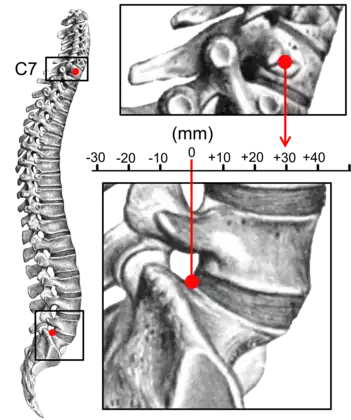

Kyphosis can be graded in severity by the Cobb angle. Also, sagittal balance can be measured. The sagittal balance is the horizontal distance between the center of C7 and the superior-posterior border of the endplate of S1 on a lateral radiograph.[7]